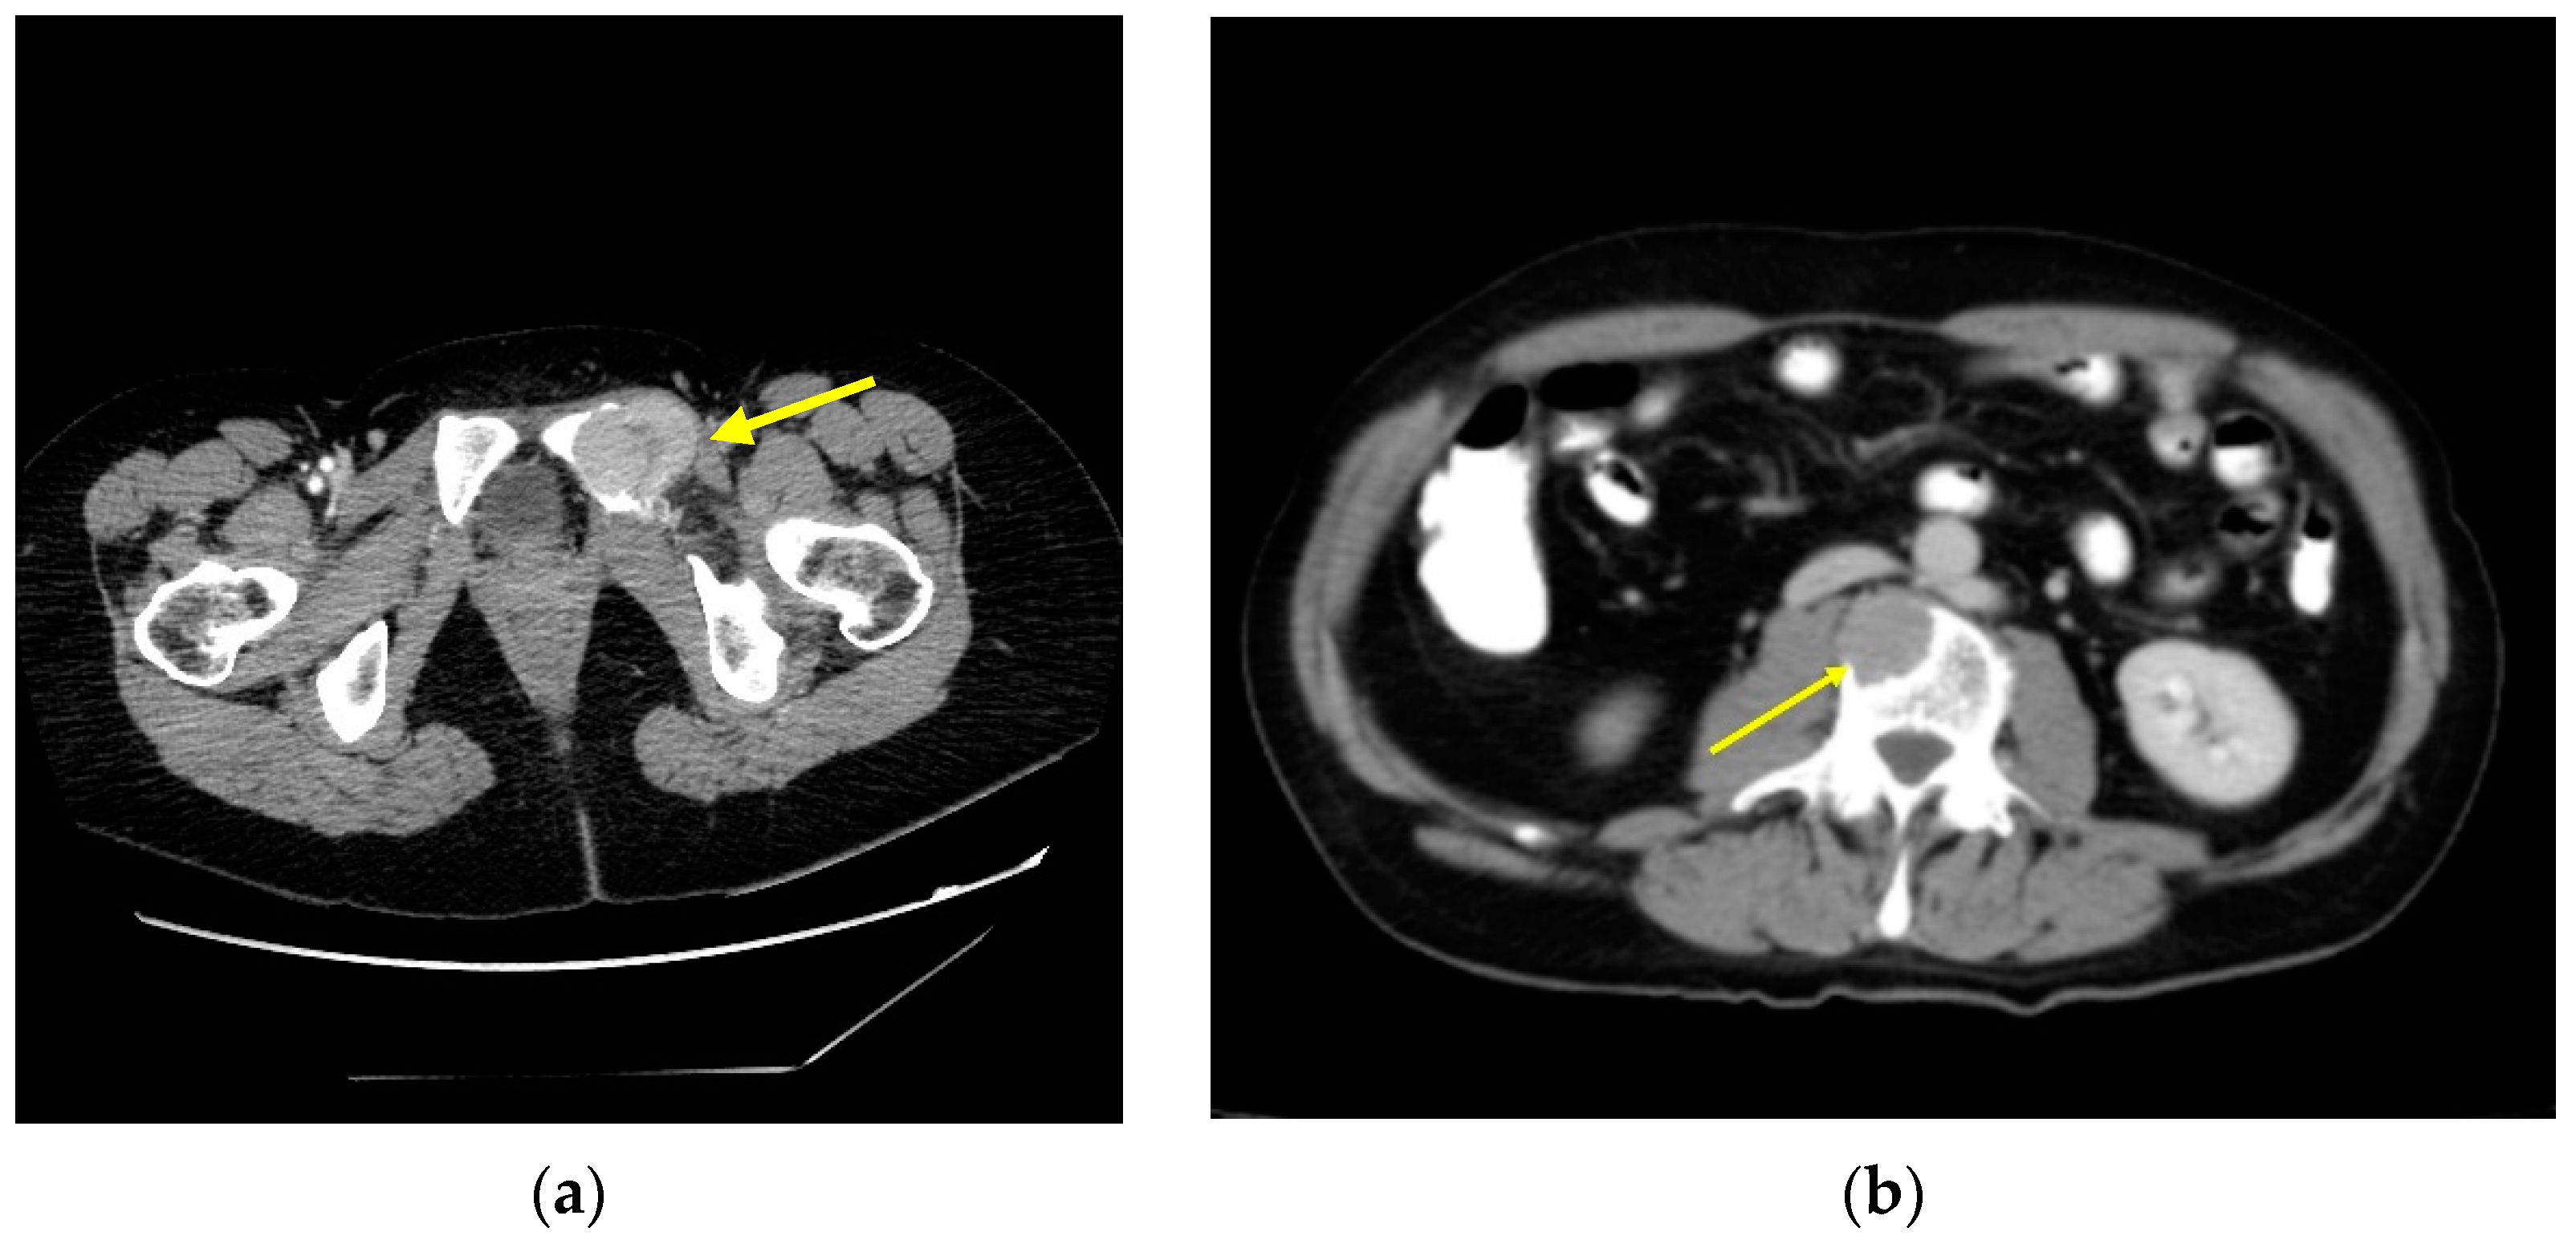

4. Neck Recurrences

5. Distant Recurrence